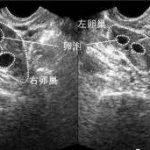

三代试管技术是一项高科技生育辅助技术。它通过采集父母和祖父母的DNA信息,进行基因筛查后,筛选出没有遗传基因缺陷的胚胎进行植入子宫。这种技术可以有效避免染色体异常、遗传病等问题。